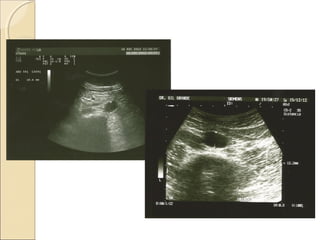

Barro biliar

ColelitiasisColelitiasis

Dolor,

postpandrial, no

pirosis, continuo,

a veces más

intenso, a veces

menos, en

paciente obeso.

¿Dónde está el Páncreas?¿Dónde está el Páncreas?